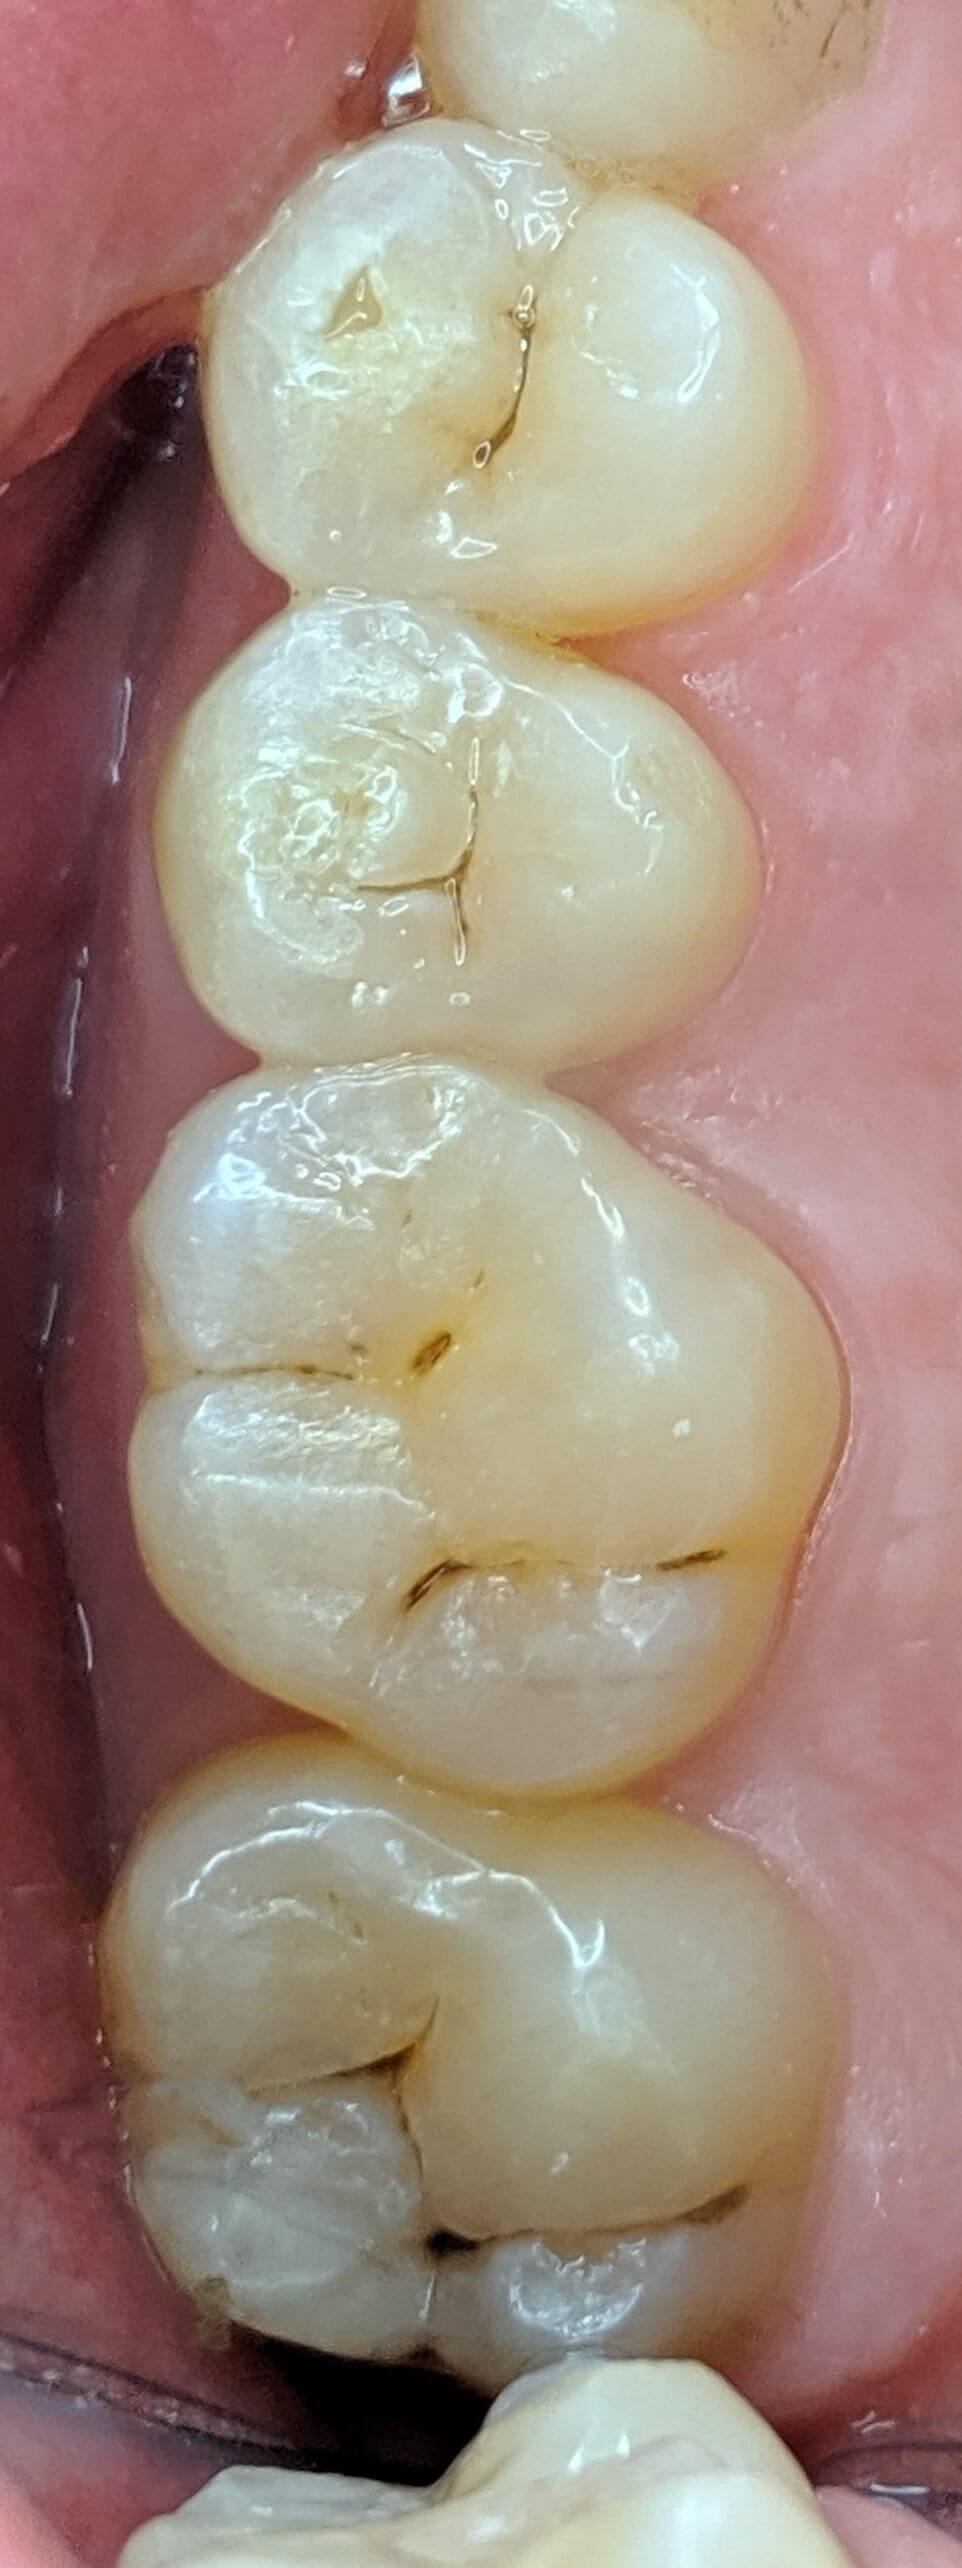

Tooth-colored fillings often fill in the decay in the enamel after it has been cleaned. Composite resin is a versatile material that can be used to treat other problems with your teeth, including cracks or enamel that has been worn down by teeth grinding (bruxism). Since the composite resin is colored to match your natural teeth, tooth-colored fillings can be used on both the front and back teeth for a seamless appearance. If you have metal fillings, talk to Dr. Kim or Dr. Chang about having them removed and replaced with tooth-colored fillings.

Getting a filling at Luminous Dental Studio is typically an easy process. The area surrounding the cavity will be numbed with a local anesthetic to minimize your discomfort. Other forms of sedation can be discussed if you have any fears or dental anxieties to help keep you at ease during the procedure. Once you are prepared, the decayed enamel is removed with a unique dental drill that Dr. Kim or Dr. Chang will select based on where the cavity is located in the tooth and the level of decay. After the enamel is removed and the tooth is cleaned, the cavity will be filled with the composite material and set with a special light. Dr. Kim or Dr. Chang will polish the filling so it feels comfortable and matches your natural teeth.

Yes, they do. The main benefit of tooth-colored fillings is the fact that they don't change the natural color of your tooth — so no one but you will know you have a filling.